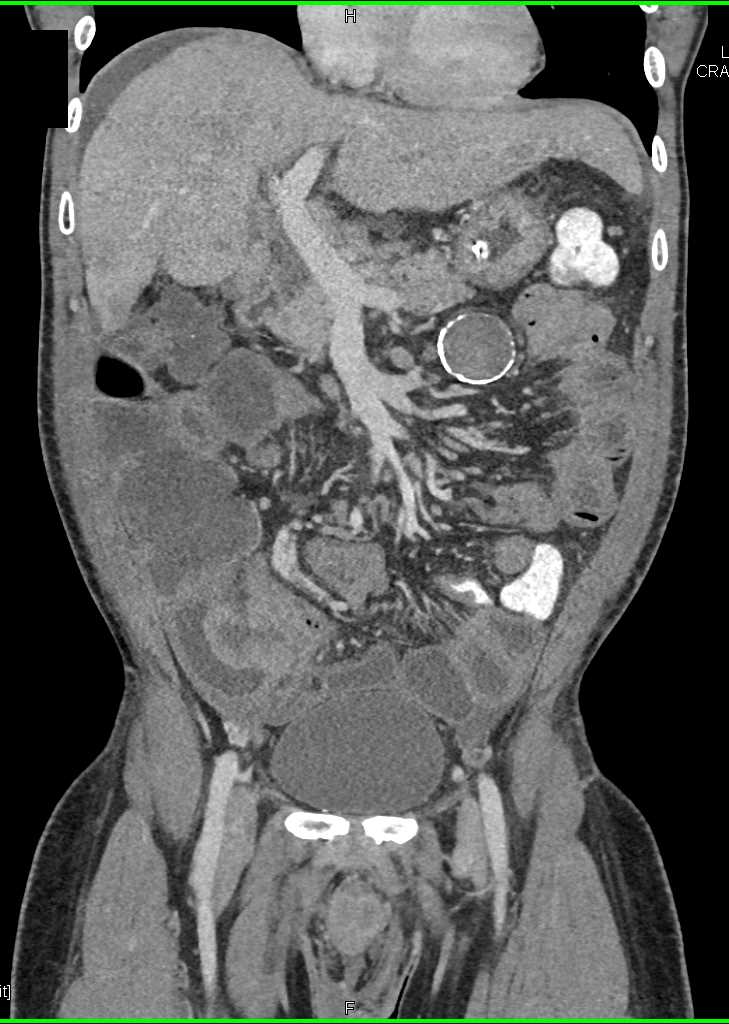

Small Bowel Carcinoma with Carcinomatosis